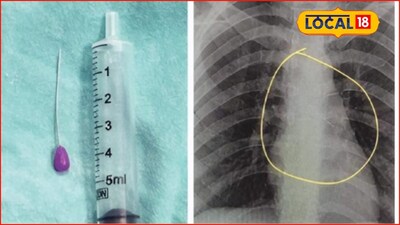

- •सीटी स्कैन से बच्चे के बाएं फेफड़े में बादाम का टुकड़ा फंसा होने की पुष्टि हुई, जिसके बाद आपातकालीन ब्रोंकोस्कोपी की गई.

- •घाटी अस्पताल के ईएनटी विभाग के डॉक्टरों ने डॉ. सुनील देशमुख के नेतृत्व में एंडोस्कोप के माध्यम से विशेष चिमटी का उपयोग करके बादाम का टुकड़ा सफलतापूर्वक निकाला.